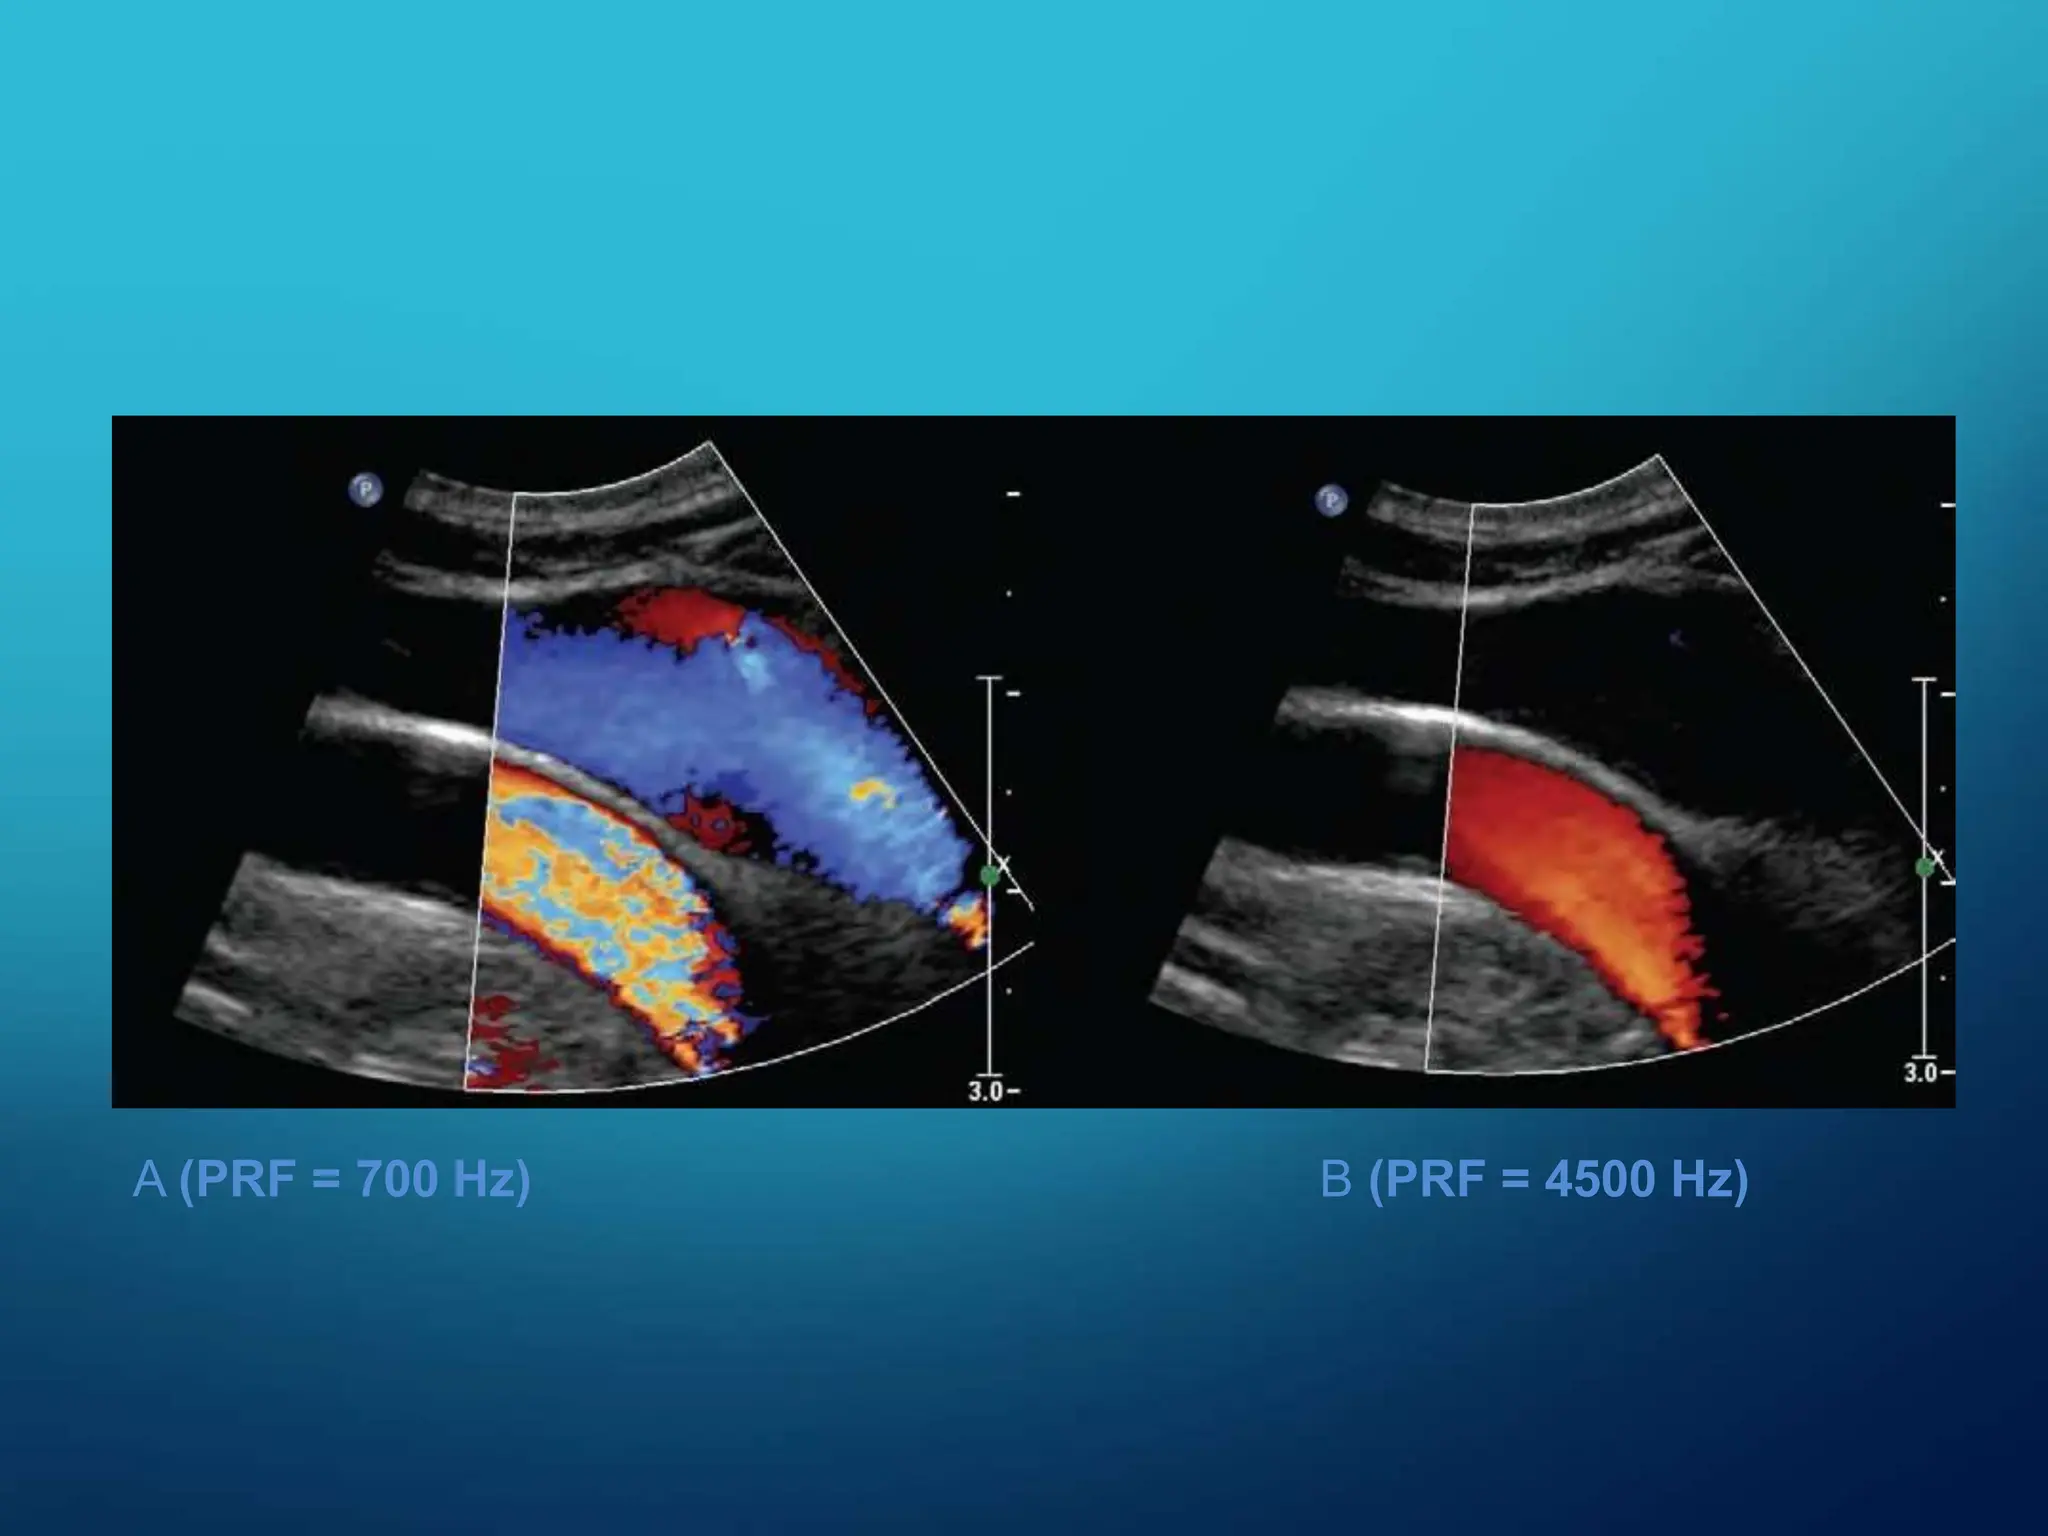

PULSE REPETITION FREQUENCY ( PRF) - No. of pulses transmitted

per second

PRINCIPLE : With increasing scanning depth PRF decreases as more time is

needed for the echoes to return

1. At a minimum, the PRF must be at least twice the frequency of the

Doppler signal to construct the signal successfully.

2. This sets upper limit to the flow velocities to be accurately recorded.

3. Use higher PRF setting for high flow velocities, low PRF for slow venous flow

A (PRF = 700 Hz) B (PRF = 4500 Hz)

A (PRF =700 Hz) B (PRF = 4500 Hz)